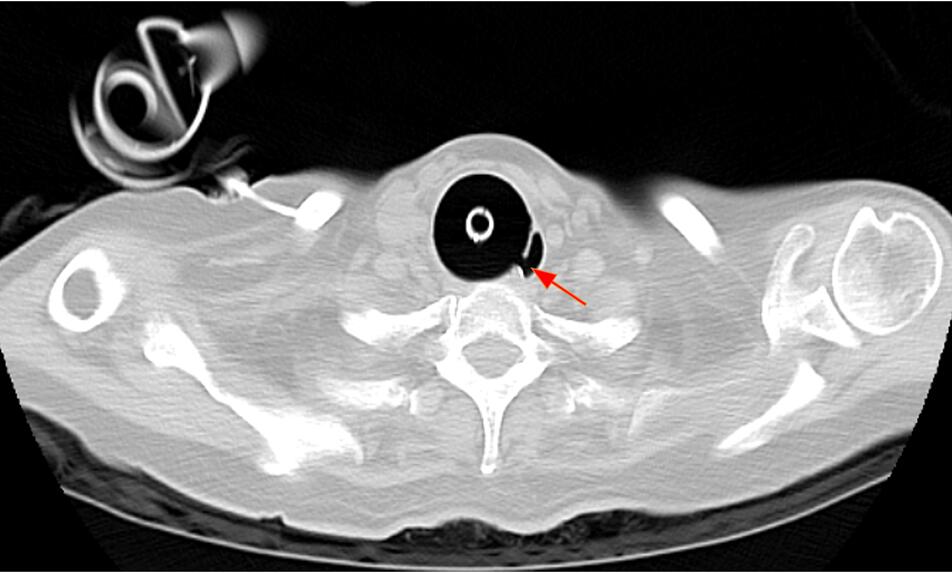

12月26日查房时可听到患者喉部有“呼噜声”,并再次出现腹胀,呼吸机报警潮气量低,分钟通气量仅3.0-3.5L,此时上级医师考虑可能出现了气管食管瘘。当时检查气管插管气囊压力,比鼻尖还软一点,可拿气囊测压表一测,大家都惊呆了,测压器显示此刻压力达到了80.3cmH2O!这远远超过了正常压力范围。为证实气管食管瘘,当天下午我们就给患者做了床边胃镜及胸部CT。

胃镜下清晰可见食管壁有一巨大的破口,气囊和气管插管“突破”重重阻碍到食管了。胸部CT和定位片都可明显看出来。

图3 12月26日胸部CT平扫